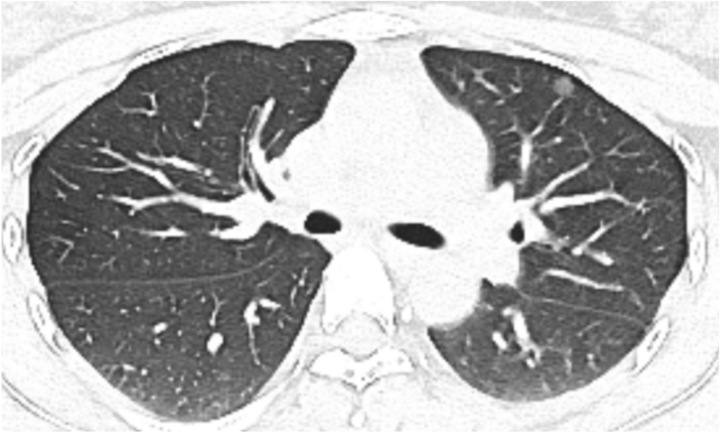

Hình ảnh kiểm tra phổi của bệnh nhân.

Chị Hoàng, một phụ nữ trẻ đang lên kế hoạch mang thai, gần đây cảm thấy khó chịu ở ngực. Trong một lần khám sức khỏe, chị quyết định chụp CT ngực để kiểm tra. Kết quả, chị có một nốt mờ khoảng 1 cm ở phổi trên bên trái.

Sau khi xem xét kỹ lưỡng phim chụp CT, bác sĩ Lưu nhận định, nốt kính mờ này nguy cơ cao là ác tính. Ông chỉ ra rằng, dù hơn 90% các nốt phổi là lành tính, nhưng hình ảnh CT của chị Hoàng cho thấy các dấu hiệu đáng ngờ như gai ngắn và vi mạch trong khối u.